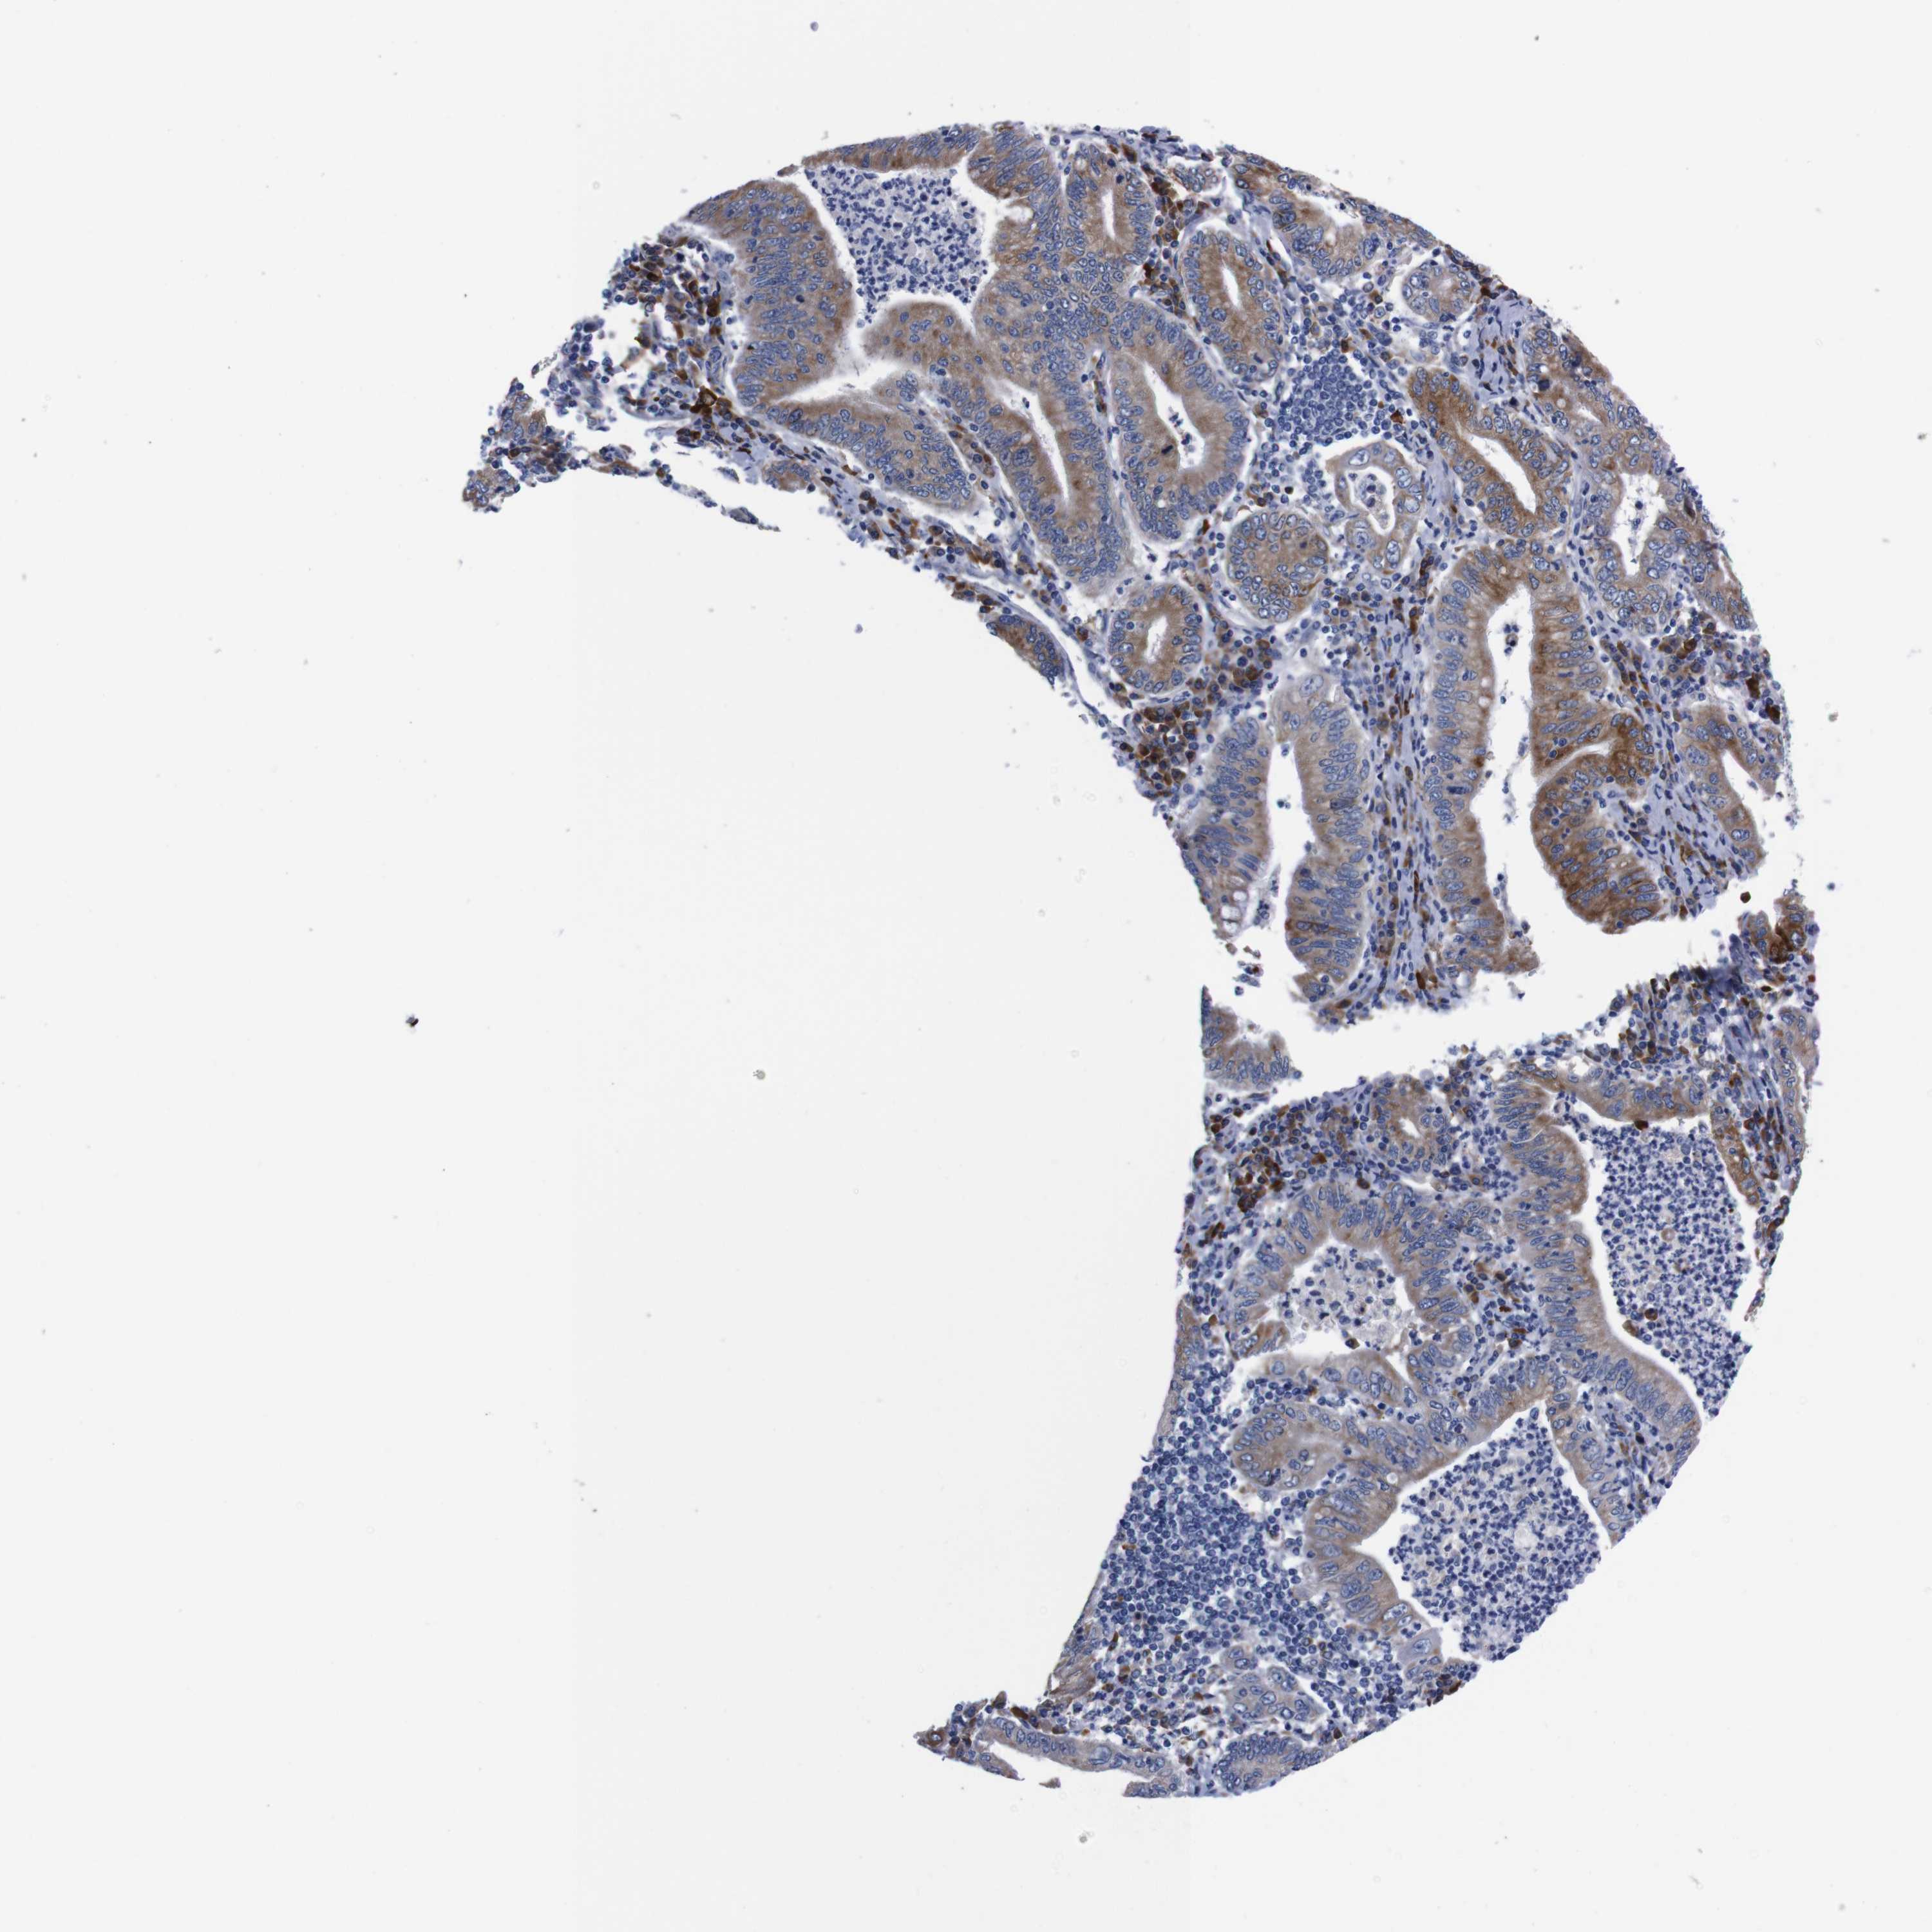

STOMACH CANCER - Protein expressioni

A mouse-over function shows sample information and annotation data. Click on an image to view it in a full screen mode. Samples can be filtered based on level of antibody staining by selecting one or several of the following categories: high, medium, low and not detected. The assay and annotation is described here.

Note that samples used for immunohistochemistry by the Human Protein Atlas do not correspond to samples in the TCGA dataset.

Antibody stainingi

Antibody staining in the annotated cell types in the current human tissue is reported as not detected, low, medium, or high, based on conventional immunohistochemistry profiling in selected tissues. This score is based on the combination of the staining intensity and fraction of stained cells.

Each image is clickable and will lead to virtual microscopy that enables deeper exploration of all samples and also displays staining intensity scores, fraction scores and subcellular localization as well as patient and tissue information for each sample.

Antibody HPA013994

Antibody HPA013995

Staining

High

Medium

Low

Not detected

Intensity

Strong

Moderate

Weak

Negative

Quantity

>75%

75%-25%

<25%

None

Location

Nuclear

Cytoplasmic/membranous

Cytoplasmic/membranous,nuclear

Adenocarcinoma, NOS

Adenocarcinoma, High grade